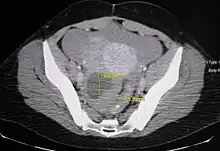

An Axial CT demonstrating a large hemorrhagic ovarian cyst. The cyst is delineated by the yellow bars with blood seen anteriorly.

Ovarian cysts are usually diagnosed by ultrasound, CT scan, or MRI, and correlated with clinical presentation and endocrinologic tests as appropriate.[10]

Follow-up imaging in women of reproductive age for incidentally discovered simple cysts on ultrasound is not needed until 5 cm, as these are usually normal ovarian follicles. Simple cysts 5 to 7 cm in premenopausal females should be followed yearly. Simple cysts larger than 7 cm require further imaging with MRI or surgical assessment. Because they are large, they cannot be reliably assessed by ultrasound alone; it can be difficult to see posterior wall soft tissue nodularity or thickened septation due to limited ultrasound beam penetrance at this size and depth. For the corpus luteum, a dominant ovulating follicle that typically appears as a cyst with circumferentially thickened walls and crenulated inner margins, follow up is not needed if the cyst is less than 3 cm in diameter. In postmenopausal patients, any simple cyst greater than 1 cm but less than 7 cm needs yearly follow-up, while those greater than 7 cm need MRI or surgical evaluation, similar to reproductive age females.[11]

For multiloculate cysts with thin septation less than 3 mm, surgical evaluation is recommended. The presence of multiloculation suggests a neoplasm, although the thin septation implies that the neoplasm is benign. For any thickened septation, nodularity, vascular flow on color doppler, or growth over several ultrasounds, surgical removal may be considered due to concern of cancer.[11]